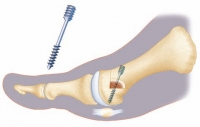

3. Stabilisierung des Großzehengrundgelenks bei Arthrose

Durch die Hallux valgus-Fehlstellung kann das wichtige Großzehengrundgelenk unter Arthrose (Gelenkverschleiß) leiden. Man bezeichnet diese als Hallux rigidus. Der Arzt kann sie entweder gelenkerhaltend behandeln (arthroskopische Cheilektomie) oder er versteift das Gelenk (Arthrodese). Daneben gibt es die Möglichkeit einer Versorgung mit Vollprothesen und Teilprothesen (Hemiprothesen).

Arthrodese: Versteifung des Großzehengrundgelenks

Schwere Hallux valgus-Fehlstellungen und Arthrose des Großzehengrundgelenks erfordern manchmal, dass das Gelenk ganz entfernt und versteift wird. Diese Versteifung erfolgt durch Fusion der beiden Gelenkpartner, die in dem Gelenk aufeinandertreffen.